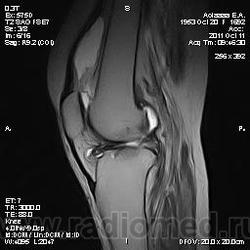

Дискуссия о природе "структры" в проекции передней поврехности метадиафиза бедренной кости.

Две версии: А. костно-хрящевой экзостоз. Б. разрастания сумки.

Я за экзостоз, но Вставьте снимки!))

Пациента на МРТ прислали с травмой. "Это" было выявлено в ряду другой патологии как случайная находка. Рентген не было возможности сделать - дистанционная диагностика. Хотя это конечно была первая мысль. Спасибо за внимание к посту.

Окончательное мнение - костно-хрящевой экзостоз. Прилагаю РКТ коленного сустава (пациент не тот, что на МРТ)

За надколенником по передней поверхности бедренной кости на МРТ и РКТ (наверное не так наглядно) - костно-хрящевой экзостоз.

+ на РКТ проекционно на уровне средней трети диафиза бедренной кости кпереди от нее - фокусы хондроматоза.

tatyana, Вы в чем то правы. Складывается впечатление что кортикальная пластинка бедренной кости почти не изменена (или не изменена вовсе). Поэтому и были сомнения. Кроме того можно отметить, что вся синовиальная оболочка бурсы тотально утолщена, что тоже наводила на определенные соменения. Наверное изменение кортикальной пластинки, которые абсолютно четко увяжут заключение с костно-хрящевым экзостозом, можно указать с "натяжкой". Скорее это волевое решение в пользу костно-хрящевого экзостоза. Еще были мнения "вилонодулярном синовиите", а также "хондроматозе". Так что возможны варианты.